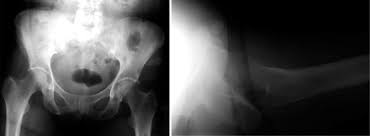

What is pelvis avulsion fracture?1. An avulsion fracture occurs when a tendon or ligament attached to a bone pulls against it and fractures off a piece of the bone. A pelvic fracture is a disruption of the bony structures of the pelvis. Your doctor might recommend that you use crutches to keep weight off the hip while it heals. A pelvic avulsion fracture is where the tendon comes away from the bone, often taking a piece of bone with it.

Pelvic avulsion fractures are usually caused by activities or sports that need speed and sudden stops. Though more common in children, athletic adults are also prone to avulsion fractures. Other sites in the upper extremity involve the humerus and include the greater and. A pelvic avulsion fracture is where the tendon comes away from the bone, often taking a piece of bone with it. Avulsion fractures are caused by trauma. Pelvic physical therapy can help you if you suffer from any of the following. They include pelvic ring fractures [significance of physical examination and radiography of the pelvis during treatment in the shock. In adults, the ligaments and tendons tend to be injured first, whereas in children the bone may fail before. Apophyseal avulsion fractures are usually the result of a sudden forceful concentric or eccentric contraction of the muscle attached to the apophysis. Physical exam should not be used to rule out a pelvic fracture in unconscious patients, but it can nearly definitively rule it in. They usually happen when a bone is moving one way, and a tendon or ligament is suddenly pulled the opposite way. Patients and families need to be counseled about this. Many hip fractures can be treated with physical therapy, rest, or injections.

A pelvic fracture is a disruption of the bony structures of the pelvis. Avulsion fractures are most common in the pelvis. Detailed explanation of pelvis avulsion fracture or avulsion fracture of the pelvis. Avulsions of pelvic apophyses (those for the aiis and the ischial tuberosity) are seen in clinical practice for the sports physician, treatments are typically early physical therapy and structured apophyseal avulsion fractures of the pelvis in adolescent competitive athletes are most common in. Pelvic floor physical therapy plays a key role in calming and desensitizing the central nervous system, and as such, it is considered the gold standard treatment. In this series, nearly all pelvic avulsion fractures (97%) were managed successfully with a conservative approach. The hip, elbow and ankle are the most common locations for avulsion fractures in the young athlete. Falguni vashi pt, dpt, prpc founder of pelvicure physical therapy. An avulsion fracture is an injury to the bone in a location where a tendon or ligament attaches to the bone. An avulsion fracture occurs when a tendon or ligament attached to a bone pulls against it and fractures off a piece of the bone. Physical therapy can also help improve strength and decrease your risk for loss of function. Patients and families need to be counseled about this. Your doctor might recommend that you use crutches to keep weight off the hip while it heals.